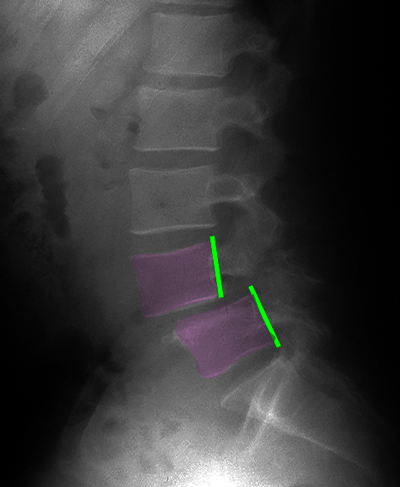

Σπονδυλολίσθηση 3ου βαθμού Ο5-Ι1, ισθμική. Η προσθιολίσθηση του Ο5 σπονδύλου επί του Ι1 απεικονίζεται με την απόσταση ανάμεσα στα οπίσθια τμήματα του σώματος των σπονδύλων (πράσινες γραμμές). Το νευρικό τρήμα παρουσιάζει σημαντική στένωση στο επίπεδο της σπονδυλολίσθησης (κίτρινος κύκλος, τρήμα με φούξια, νεύρο με μπλέ) σε σχέση με το άνωθεν αυτού φυσιολογικό (κυανό βέλος). |